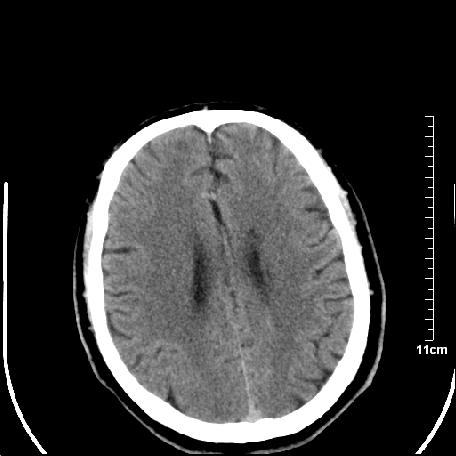

外伤患者,什么病,

外伤患者,没什么症状,

双侧外侧裂,左侧脑沟见高密度结节影,边清,还有鞍上池层面密度也高

1.左额叶脑软化灶。

2.老年脑,基底动脉硬化迂曲。

基底动脉硬化迂曲。高血红蛋白血症。